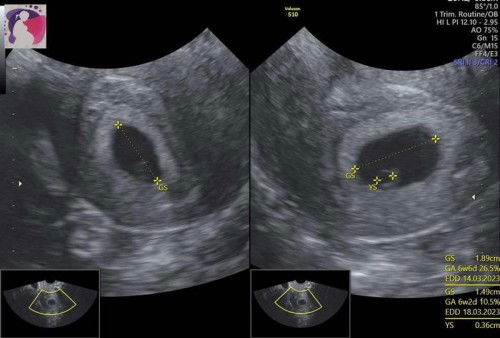

Sudah ada kantung janin dan YS , tapi belum terlihat janin 🥺

Kalo Menurut hpt ku 7week, ternyata dari usg 6week ( karna jadwal haid yg tidak terlalu teratur) , tp sedih td janinnya belum ada, tapi YS (tempat nutrisi janin) sudah ada, disuruh balik lagi 2 minggu lagi, apakah ada yg seperti ini? Optimis dedenya muncul, mohon doanya ya bunda bunda 🙏🏼🙏🏼#firstmom #firstbaby